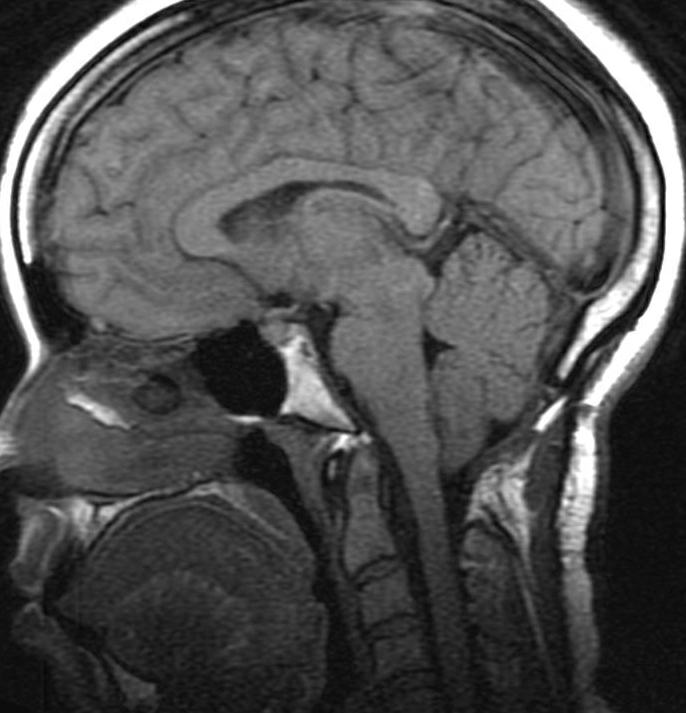

30yo with recurrent persistent headaches Prior surgical history: Chiari decompression (didn't help), pituitary surgery (normal tissue) This is a subtle diagnosis that was initially overlooked. What do you suspect? Answer to follow

IIH #radres